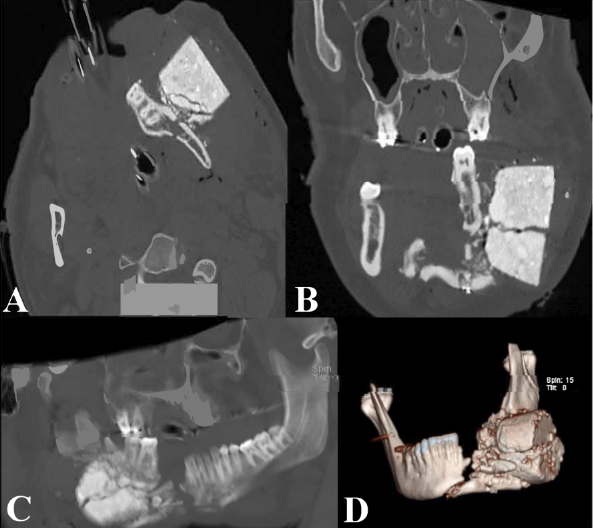

A 23-year-old man presented after a mortar misfired and propelled the ignited aerial shell of a firework toward his face, becoming lodged in his left jaw. His neighbor, a veteran and previous combat medic, expeditiously applied pressure and wet rags to prevent the ignited aerial shell from exploding. The patient was intubated upon arrival at the hospital, and after being stabilized, imaging was obtained (Figure 1).

As the ignited aerial shell had yet to explode, the bomb squad was notified. Using explosive precautions, a tracheostomy was performed to allow improved access and careful removal of the undetonated explosive (Figure 2). The nonviable tissue was excised, and the patient was secured in premorbid occlusion. Mini-plates were used to approximate comminuted segments. A large, spanning reconstruction plate was shaped and placed across all fractures. Bone allograft was used to fill defects, and the wound was closed primarily (Figures 3 and 4). Further operations were required for additional bone grafting, perioral contracture release, scar revisions, and removal of the submandibular gland due to recurrent ranula formation.